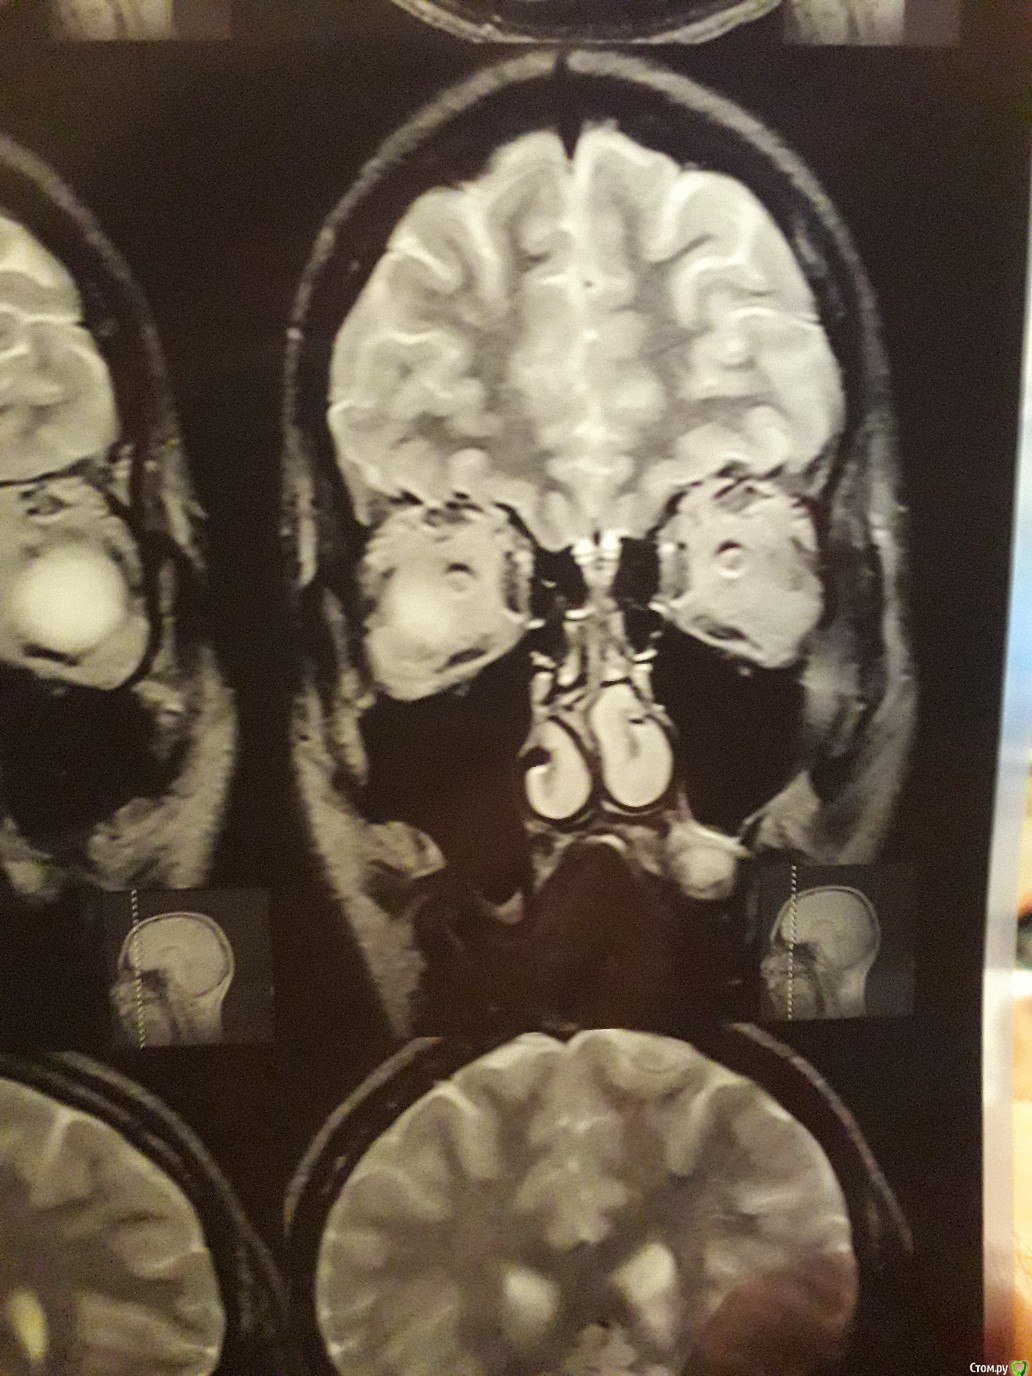

Виталий000000001 Опубликовано 30 сентября, 2017 Поделиться Опубликовано 30 сентября, 2017 Здравствуйте. На корне 26-го зуба киста вросшая в гайморову.Одни врач посоветовал удалить;Второй - не трогать и понаблюдать, если не беспокоит;А третий хирург сказал, что при удалении зуба, такая большая киста останется в кости и продолжит расти и что такое лечится только операцией на гайморовой.Подскажите что делать с кистой. Ссылка на комментарий

red_butler Опубликовано 1 октября, 2017 Поделиться Опубликовано 1 октября, 2017 По этим снимкам ничего не скажешь. Делайте кт на стоматологическом томографе 1 Ссылка на комментарий

IvanK Опубликовано 2 октября, 2017 Поделиться Опубликовано 2 октября, 2017 Перфорируется ли гайморова при удалении этого зуба?скорее нет, чем да По этим снимкам ничего не скажешь. Делайте кт на стоматологическом томографе+1 Ссылка на комментарий